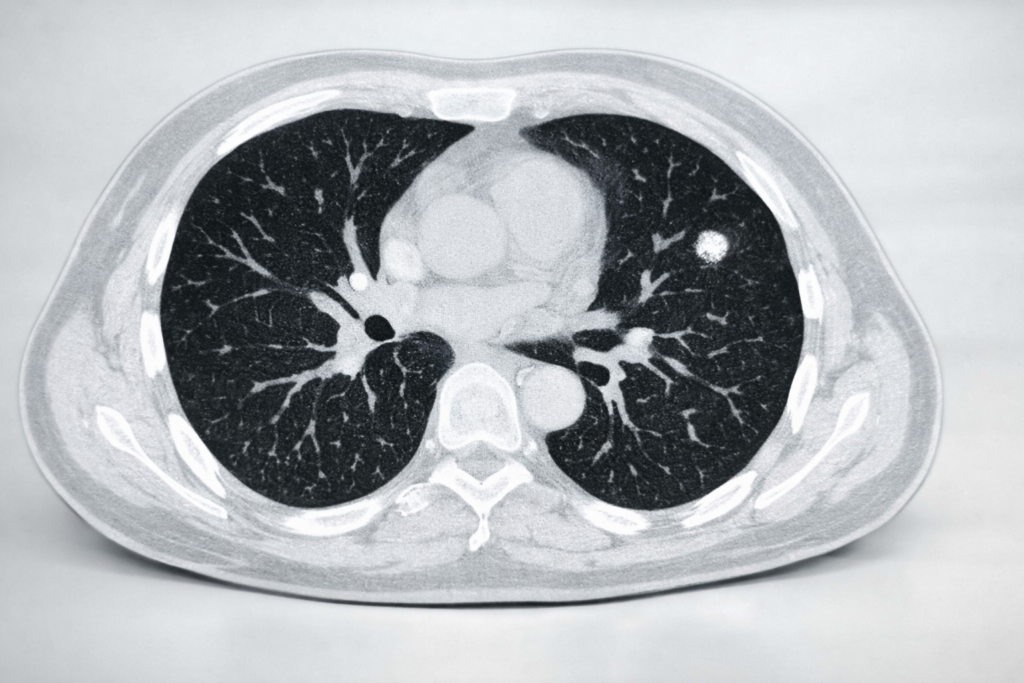

폐결절 크기별 관리 원칙을 확인하세요. 6mm 결절의 수술 필요성과 추적 관찰 시 주의사항을 현직 간호사가 환자 입장에서 상세히 설명해 드립니다.